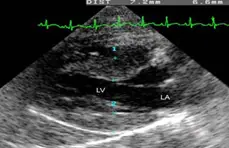

Klinički simptomi mačke sa HCM-om uključuju simptome od jedva zamjetnog porasta frekvencije disanja do vrlo otežanog disanja, paralize stražnjih ekstremiteta te iznenadne smrti u mačke koja se do nedavno doimala posve zdravom. Mnoge mačke razviju srčani šum, galopirajući ritam i/ili povišenu srčanu frekvenciju koju veterinar može uočiti prilikom rutinskog kliničkog pregleda. Ultrazvučna pretraga srca uz upotrebu Dopplera najosjetljivija je i jedina sigurna metoda dijagnostike HCM-a, dok dodatne pretrage poput EKG ili RTG-a mogu kliničara samo opskrbiti dodatnim podacima.